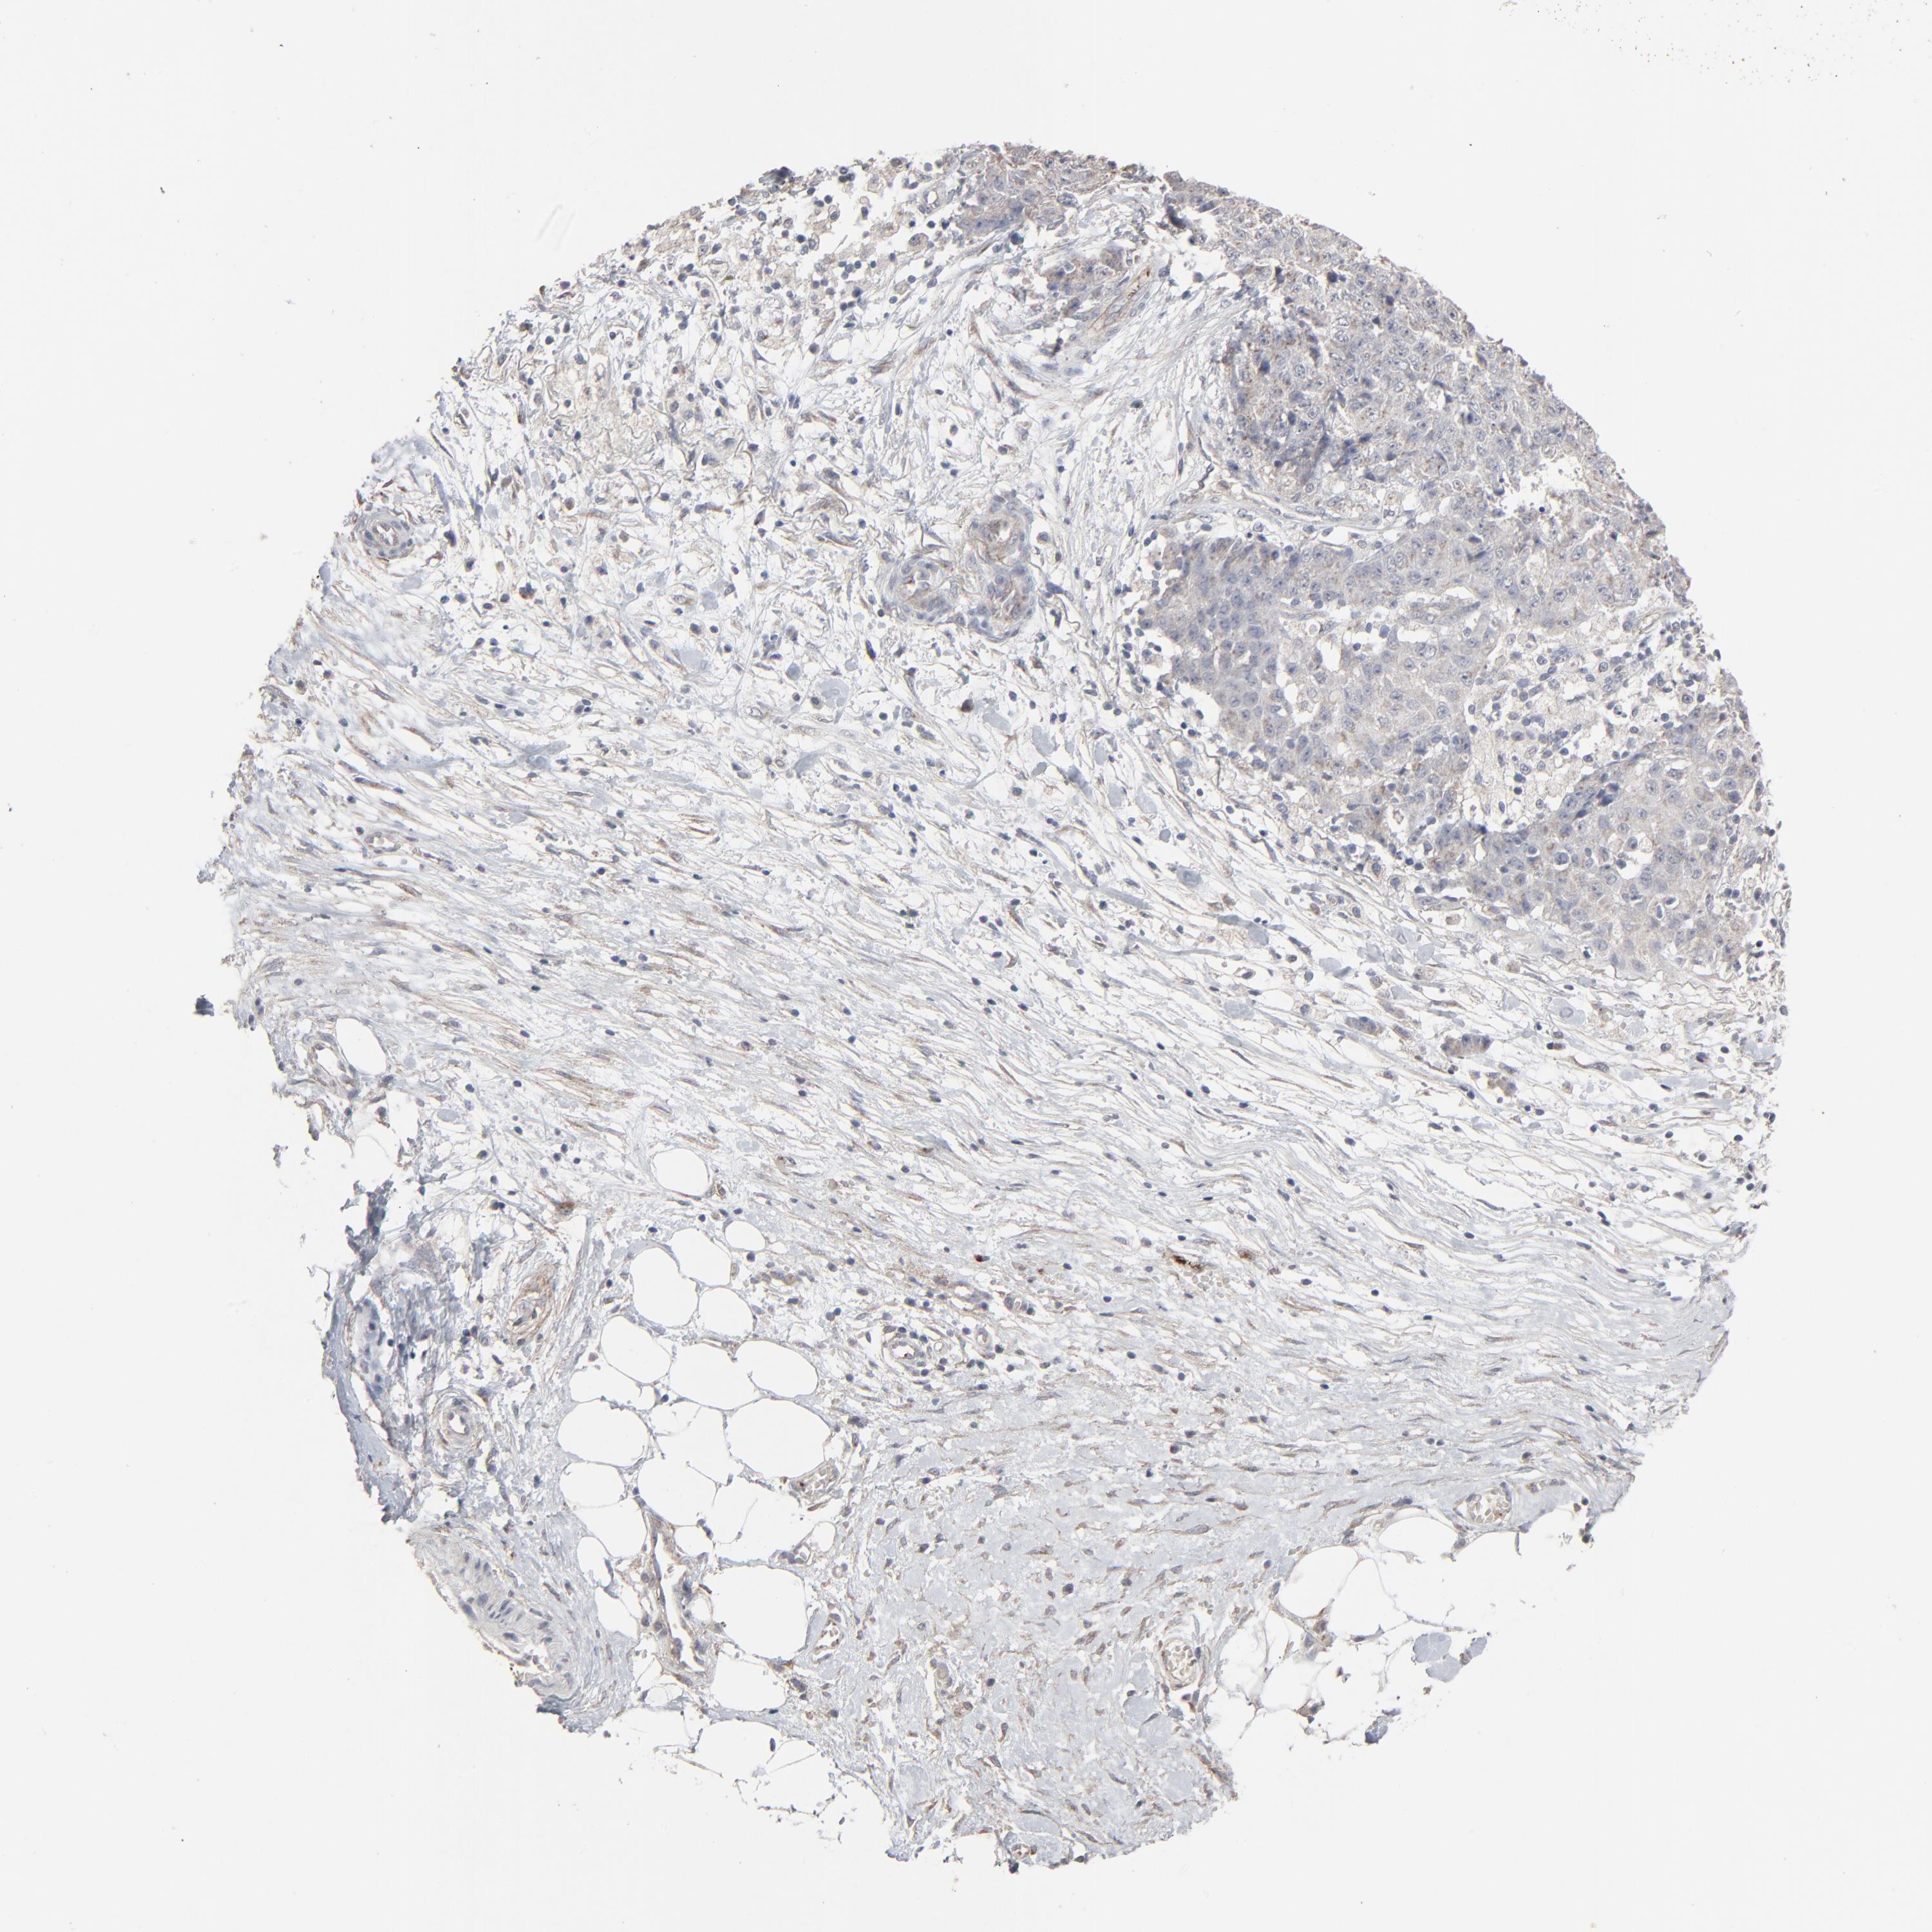

OVARIAN CANCER - Protein expressioni

A mouse-over function shows sample information and annotation data. Click on an image to view it in a full screen mode. Samples can be filtered based on level of antibody staining by selecting one or several of the following categories: high, medium, low and not detected. The assay and annotation is described here.

Note that samples used for immunohistochemistry by the Human Protein Atlas do not correspond to samples in the TCGA dataset.

Antibody stainingi

Antibody staining in the annotated cell types in the current human tissue is reported as not detected, low, medium, or high, based on conventional immunohistochemistry profiling in selected tissues. This score is based on the combination of the staining intensity and fraction of stained cells.

Each image is clickable and will lead to virtual microscopy that enables deeper exploration of all samples and also displays staining intensity scores, fraction scores and subcellular localization as well as patient and tissue information for each sample.

Antibody HPA003417

Staining

High

Medium

Low

Not detected

Intensity

Strong

Moderate

Weak

Negative

Quantity

>75%

75%-25%

<25%

None

Location

Nuclear

Cytoplasmic/membranous

Cytoplasmic/membranous,nuclear

Cystadenocarcinoma, serous, NOS

Cystadenocarcinoma, mucinous, NOS

Carcinoma, endometroid